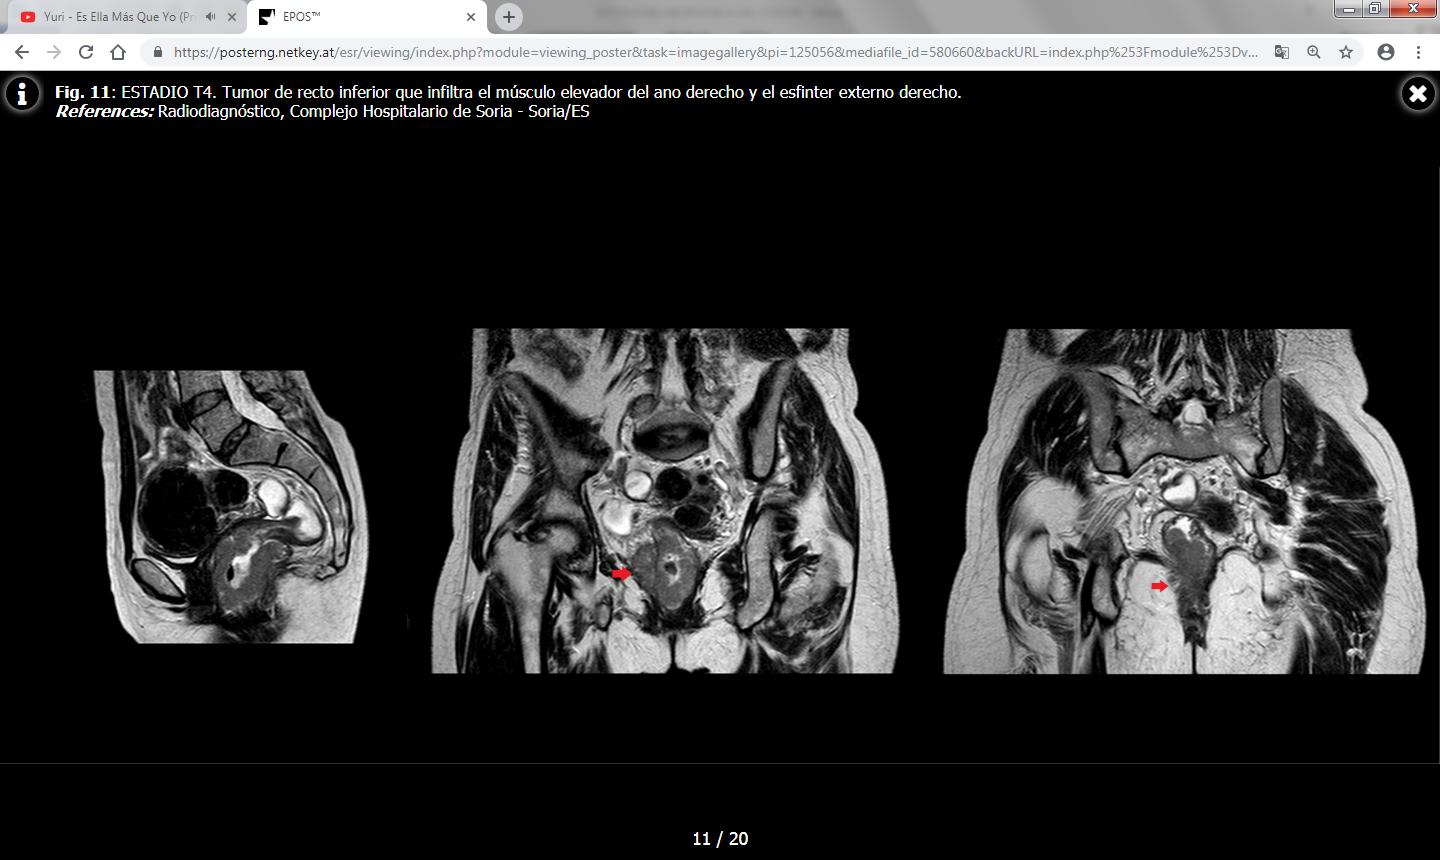

Los hallazgos en TC incluyen una masa de densidad de partes blandas de contornos irregulares o un engrosamiento parietal focal asimétrico que condicionan estenosis de la luz colónica. Las masas de mayor tamaño pueden presentar un centro necrótico de baja atenuación y ocasionalmente pueden contener gas.